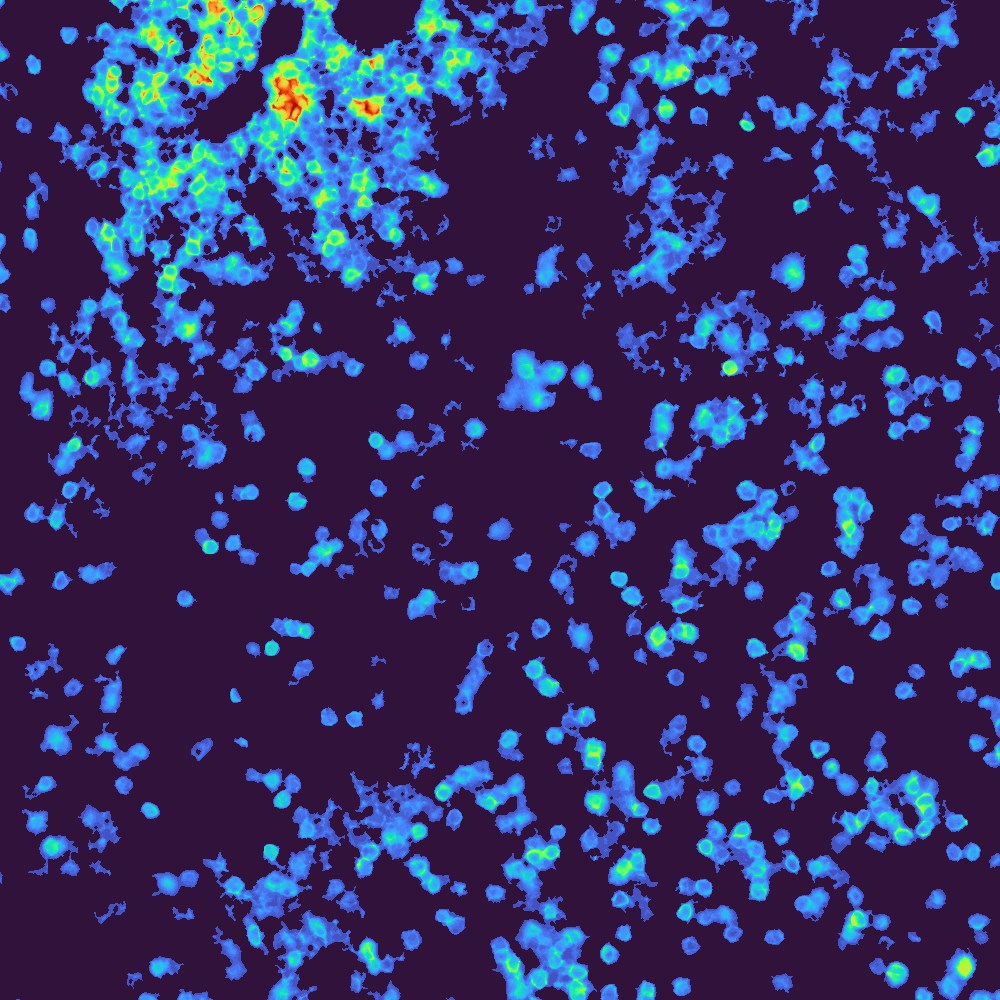

Multiplex image processing for challenging datasets with a focus on user integration rather than automation. This pipeline includes 2D/3D GPU/CPU illumination correction, stitching, deconvolution, extended depth of focus, registration, autofluorescence removal, segmentation, clustering, and spatial analysis.